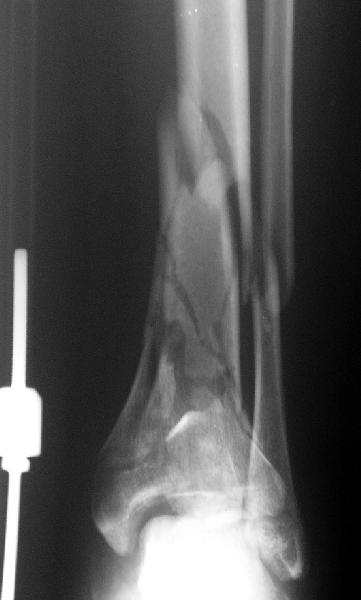

Re: Открытый оскольчатый внутрисуставной перелом д

Возможный альтернативный способ : накостный остеосинтез м/берцовой кости, открытый чрескостный остеосинтез эпиметафиза б/берцовой кости.